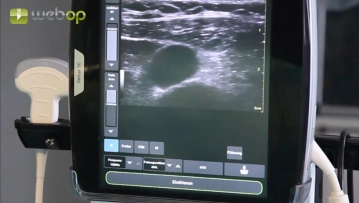

Ultrassonografia Duplex da Veia Jugular Interna Direita, Anestesia Local

Após a desinfecção da pele e o drapejamento estéril, a ultrassonografia duplex é realizada com o propósito de localizar a veia jugular interna. Não mostrado no clipe é a anestesia local, que abrange o lado selecionado do pescoço, todo o túnel subcutâneo e o local de saída percutânea posterior do cateter infraclavicularmente. Tipicamente, são necessários 10-15 ml de anestésico local (p.ex., Xylonest® 1%).

Configurações de som Sob orientação ultrassonográfica, a punção da veia jugular interna é realizada com a cânula de Seldinger. Inserção do fio-guia.